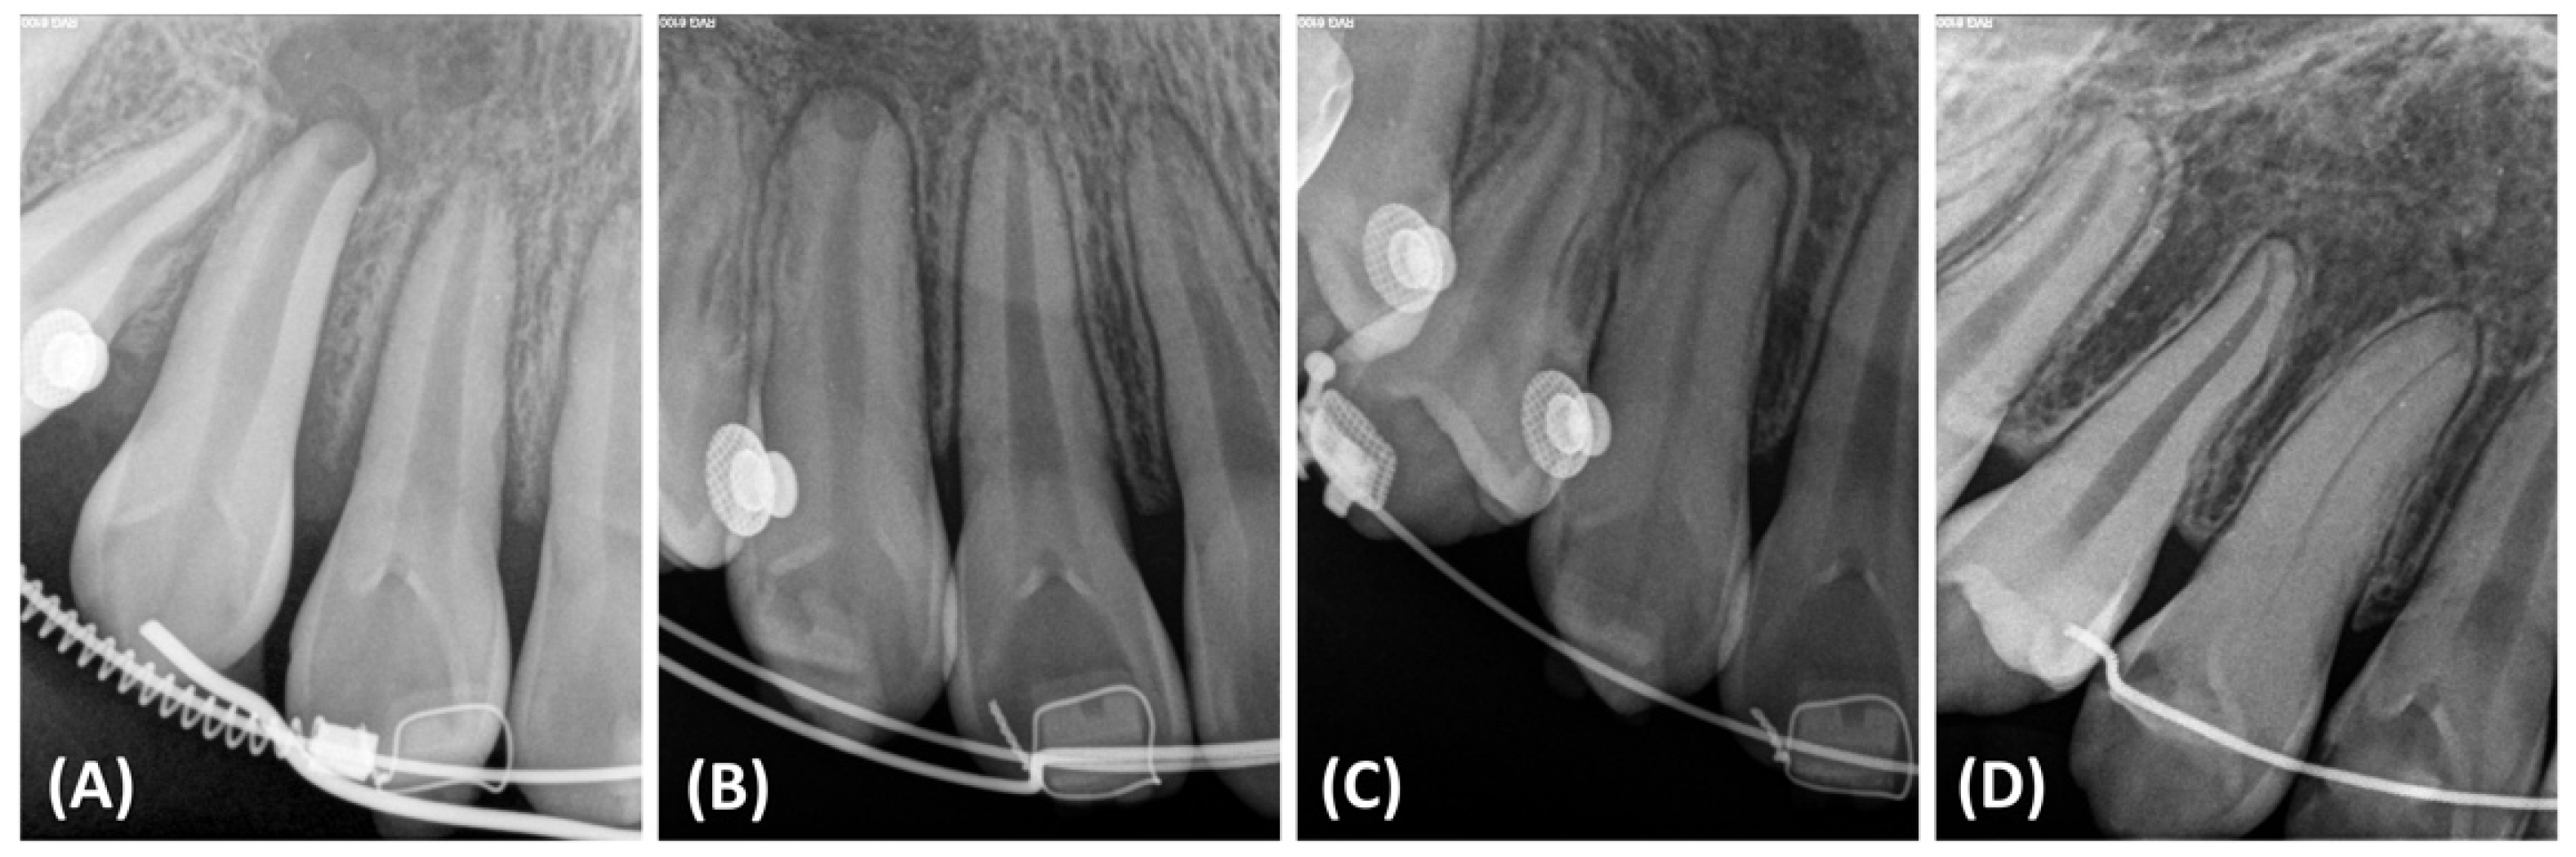

2.4. Treatment Progress